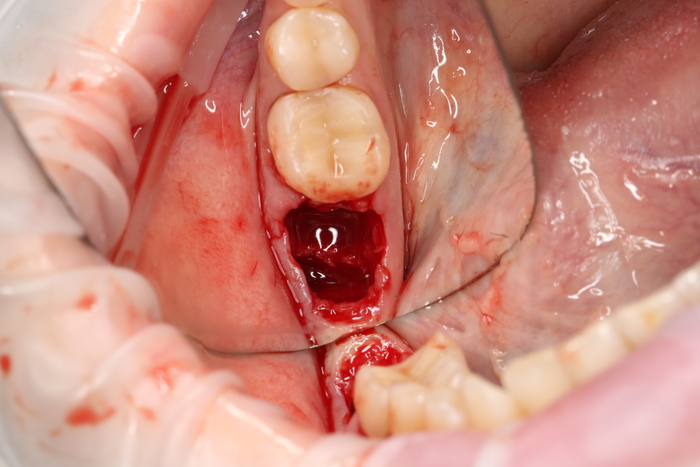

Но мне повезло, ко мне на прием пришла прекрасная девушка (а не усатый господин в плаще на голое тело) с ужасной, с ее слов, проблемой. Когда-то давно ей поставили имплантат в области верхнего бокового резца, но в связи с тем, что положение имплантата было неправильным, а одномоментно с имплантацией пластики десны не проводилось, последняя начала постепенно «подниматься», оголился абатмент (та часть, «за которую держится коронка»). Со слов пациентки, тем же доктором была предпринята попытка сделать пластику десны, не снимая этой коронки. Но, увы, развился некроз, что только усугубило ситуацию.

На момент моего осмотра это выглядело так:

После снятия коронки:

Выкрутили абатмент:

Установлена заглушка, которая закрывает шахту имплантата.